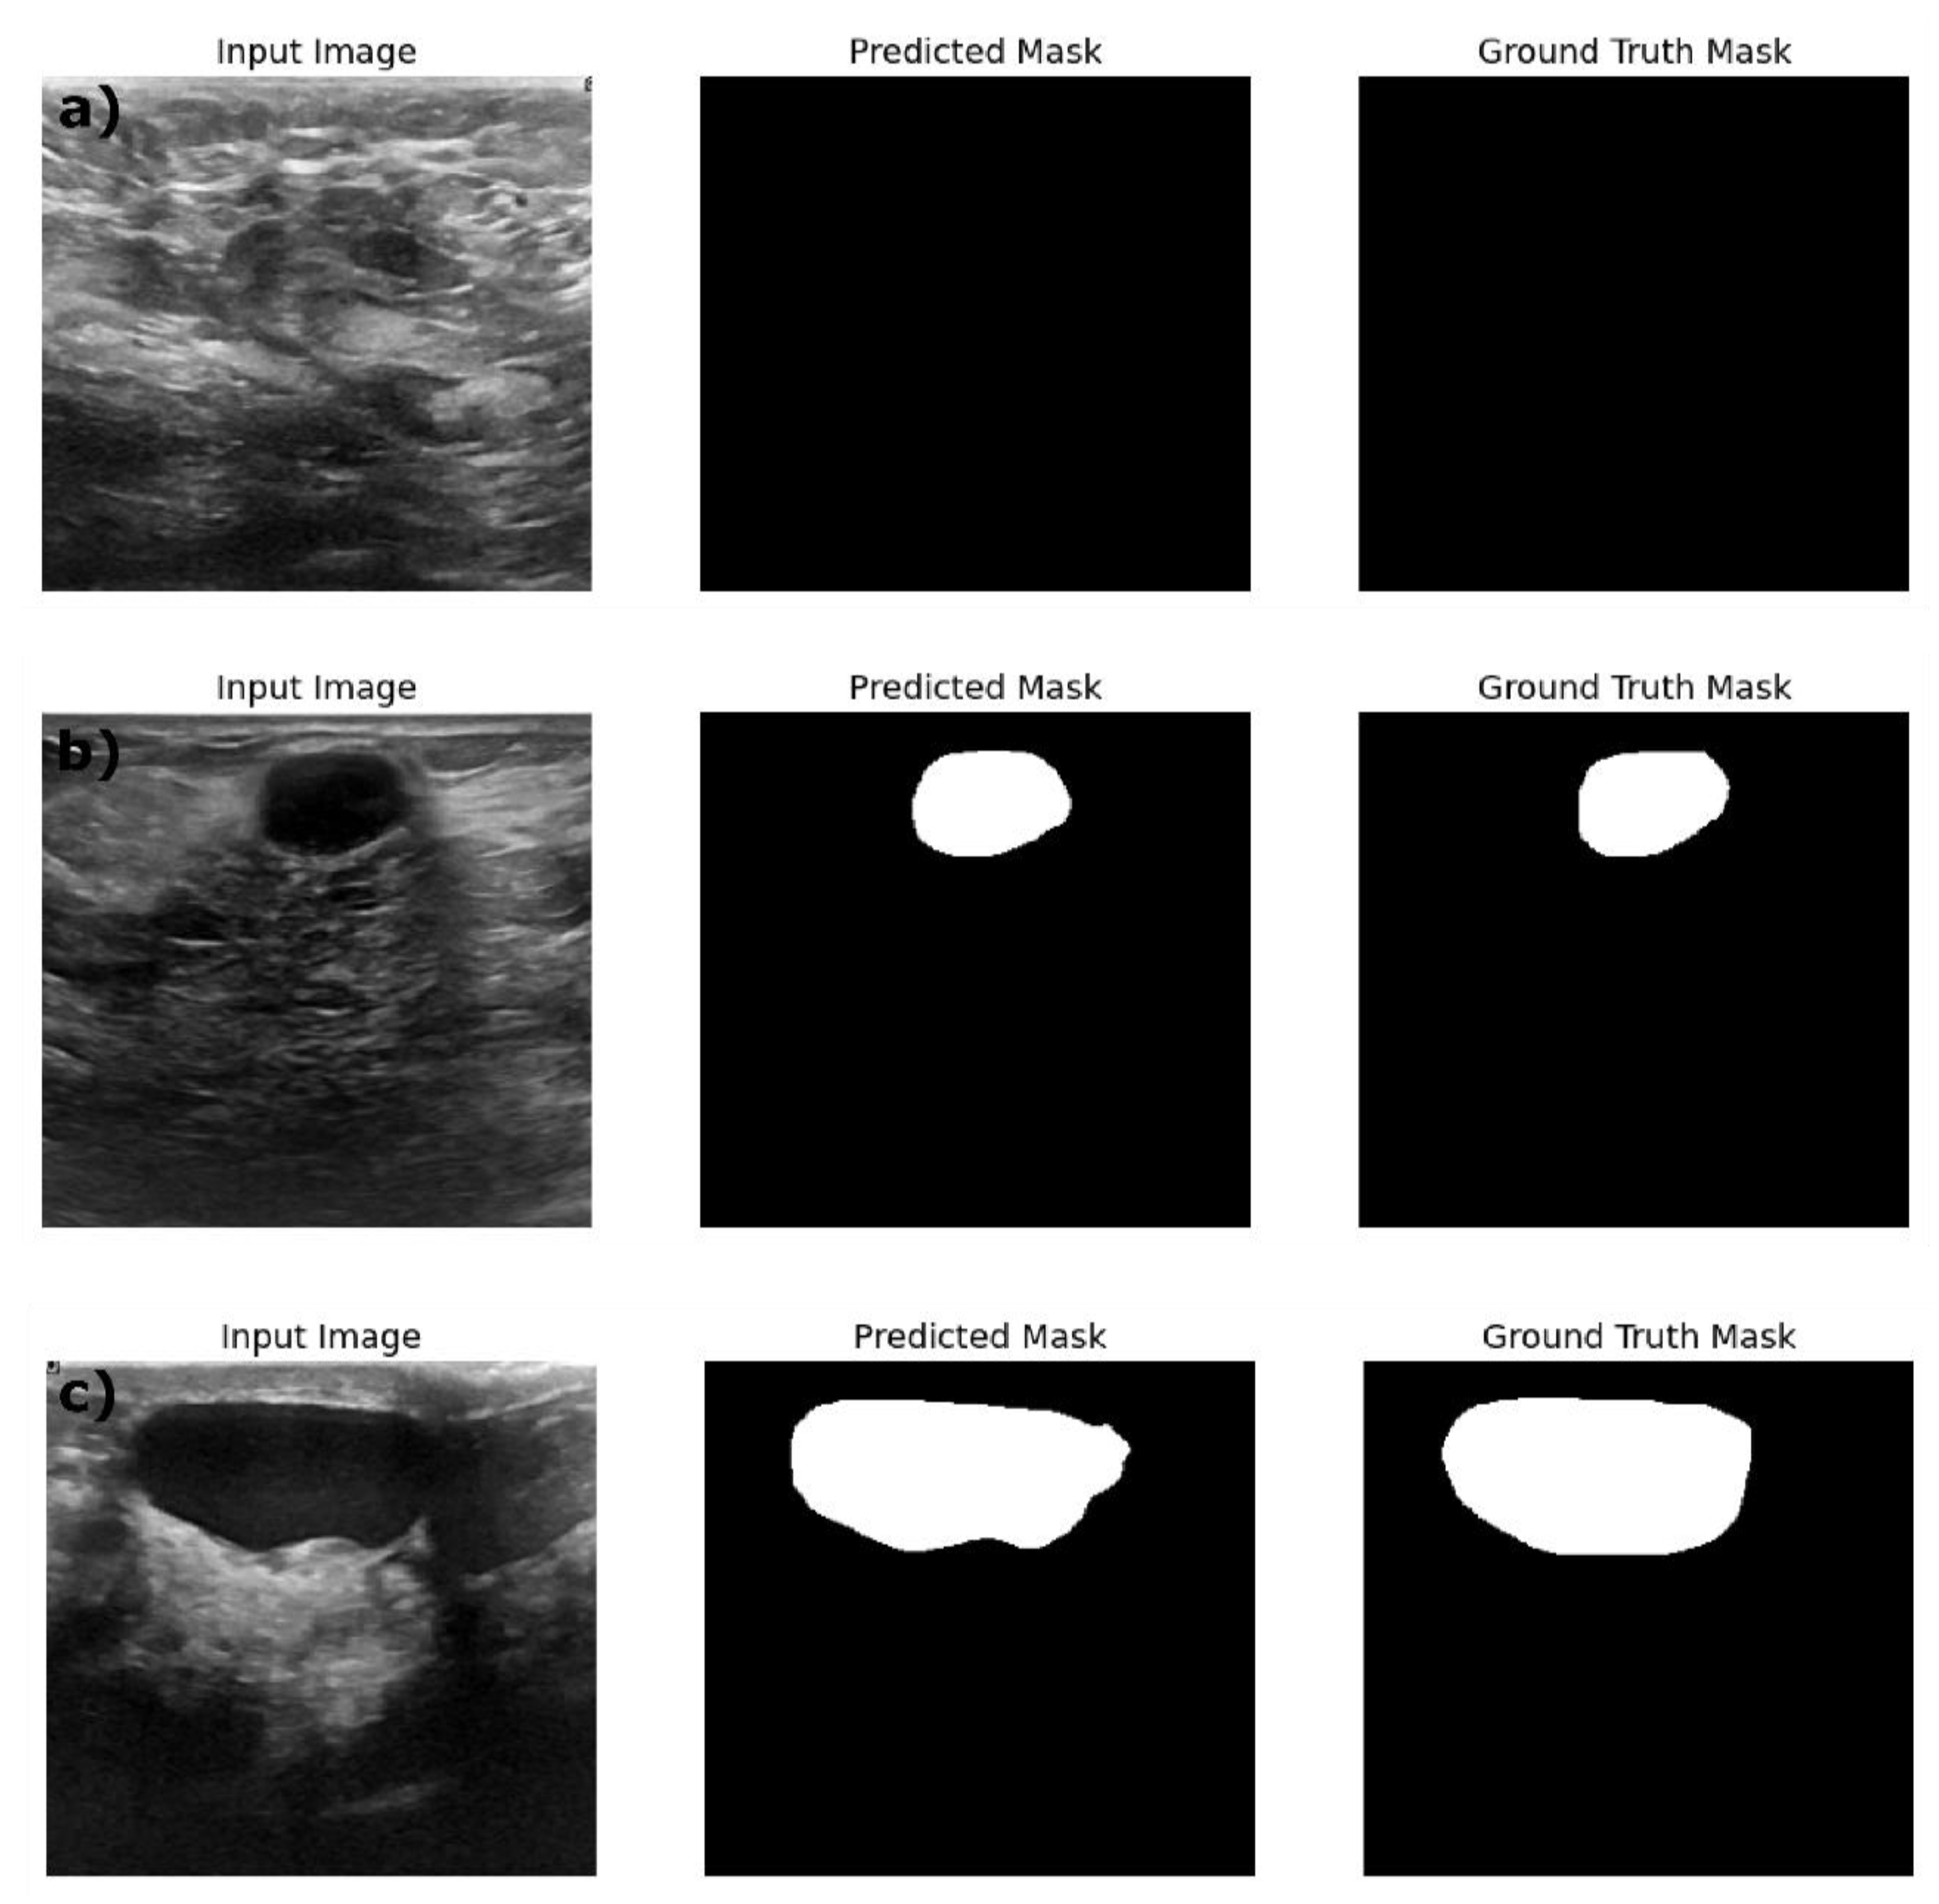

Table 4 shows the performance of the optimized image segmentation models on the train, validation and test datasets. The ResNet18:U-Net achieved a high pixel accuracy of 0.97 on the training set with a Dice Coefficient of 0.86 and IoU of 0.76 indicating that this model is performing well in terms of capturing the relevant pixels and achieved good performance on the training images and masks. Yet Resenet18: U-Net model showed an overfitting to the training dataset with decreased performance on the validation and test datasets. The Dice Coefficient dropped to 0.76 and 0.74 and the IoU to 0.62 and 0.59 respectively on the test datasets. This poor performance on the validation and test data indicates the model is struggling to generalize on the unseen dataset. This trend is reflected in the AUC score decreasing from 0.91 in training data to 0.85 and 082 on the validation and test datasets. By observing the sample segmentation results (figure3) of the ResNet18:U-net, it can be determined that the model has produced reasonably accurate in segmenting both large and small structures, however, it shows edge irregularities and slight over segmentation visible in larger structures in the test data image sample (Figure 3c). Compared to ResNet18:U-Net, Resnet18:U-Net++ achieved a better generalization on the test and validation datasets with improved Dice Coefficient and IoU scores. On the training dataset, ResNet18: U-net++ achieved better performance with high pixel accuracy of 0.98, Dice Coefficient of 0.87 and IoU of 0.77 similar to ResNet18:U-net performance. However, ResNet18:U-Net++ showed relatively higher Dice coefficient of 0.83, IoU of 0.71 and AUC score of 0.91 suggesting Resnet18:U-net++ architecture mitigates overfitting better than ResNet18:U-net especially when applied to unseen dataset. In comparison with results reported Almajalid et al [42], who achieved an average Dice score of 82.5% using U-Net based segmentation framework on the BUSI dataset of 221 images, our ResNet18: UNet++ model achieved a Dice Coefficient of 83%. They highlighted U-Net’s robustness and adaptability to ultrasound image segmentation, which supports our findings well. Similarly, our results obtained with U-Net are similar with results reported by Byra et al., They reported a Dice score of 0.77 on the validation dataset [44] while our U-Net architecture achieved a Dice score of 0.76 on the validation dataset. However, our results report the importance of the advanced architectural variations and advanced models such as ReseNet18: DeepLabV3

Figure 4 provides the sample results of the ResNet18:U-Net++ architecture on the train (a), validation (b) and test datasets (c); and Figure 4, illustrates that the ResNet18:U-Net++ model accurately segments across different sizes and shapes. ResNet18: DeepLabV3 model yielded the highest performance overall, with pixel accuracy of 0.98 on both training and test data sets. The Dice coefficient on the train, validation and test datasets are 0.87, 0.80 and 0.83 respectively. The ResNet18:DeepLabV3 outperformed ResNet18: U-Net++ in terms of Dice coefficients and IoU on training dataset. Also, the ResNet18: DeepLabV3 maintained high accuracy on test data, and it achieved highest Dice coefficient and IoU indicating that ResNet18: DeepLabV3 generalizes better on validation data than other developed models. Our ResNet18:DeepLabV3 results align with results reported in the literature, Badawy et al., reported a mean IoU value of 0.49 before applying fuzzy logic preprocessing (Badawy et al., 2021), our best segmentation model (ReseNet18:DeepLabV3) showed a mean IoU of 0.7. Similarly, they reported the developed U-net model has a mean IoU of 0.49 while the U-net model we developed has a mean IoU of 0.65. From figure 5, it is evident that the DeepLabV3 has striking balance between the robustness and precision in segmenting large irregular shaped lesions, medium and small lesions with high accuracy and detailed delineation of the edges.

Figure 3. Example predictions of the ground truth mask by Resent 18: Unet model on a) Train dataset, b) Validation dataset and c) Test dataset.

Figure 4. Example predictions of the ground truth mask by Resent 18: Unet++ model on a) Train dataset, b) Validation dataset and c) Test dataset.